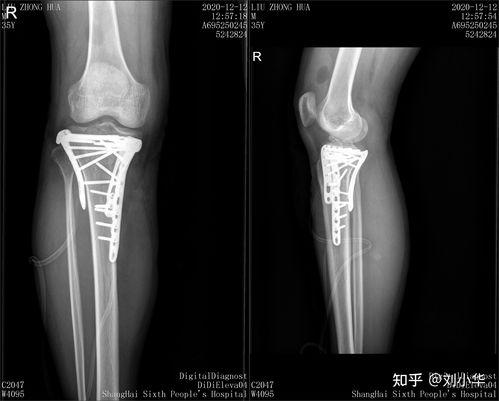

胫骨平台是位于胫骨上端的一个平台,与股骨的髁部形成膝关节。胫骨平台骨折是指胫骨平台部位发生的骨折,可能是由于直接撞击、跌倒或扭伤等原因引起。根据骨折的严重程度和位置,可分为多种类型,如单纯骨折、粉碎性骨折等。